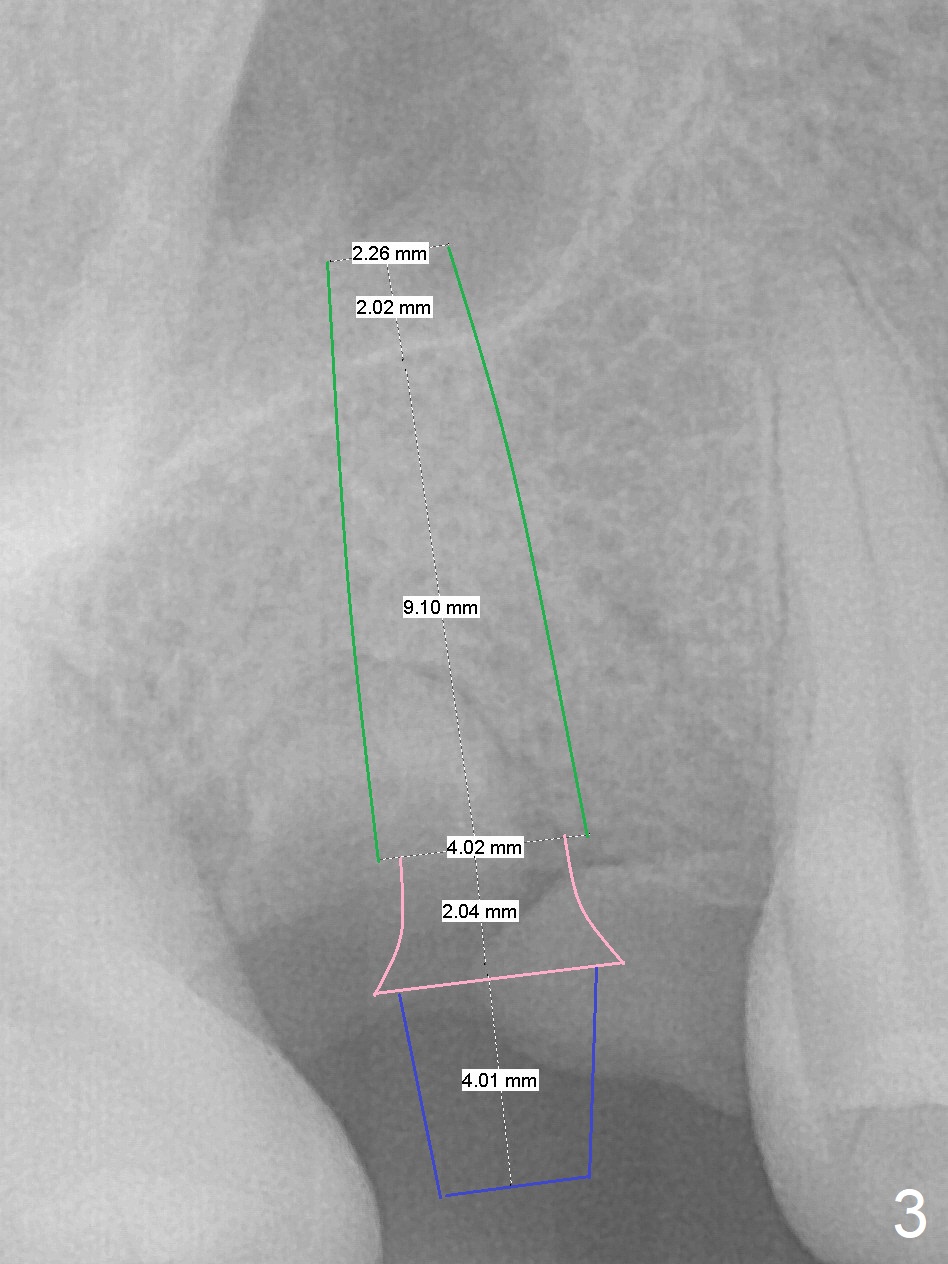

A 45-year-old woman has poor dentition due to dental phobia (Fig.1). The tooth #3 has residual roots (Fig.2 *). The initial depth will be 9 mm with starter drill, 2 mm drill (parallel pin, PA) and 3.2 mm Magic Drill (Fig.3). Use 4x11 mm dummy implant for sinus lift for the last 2 mm.